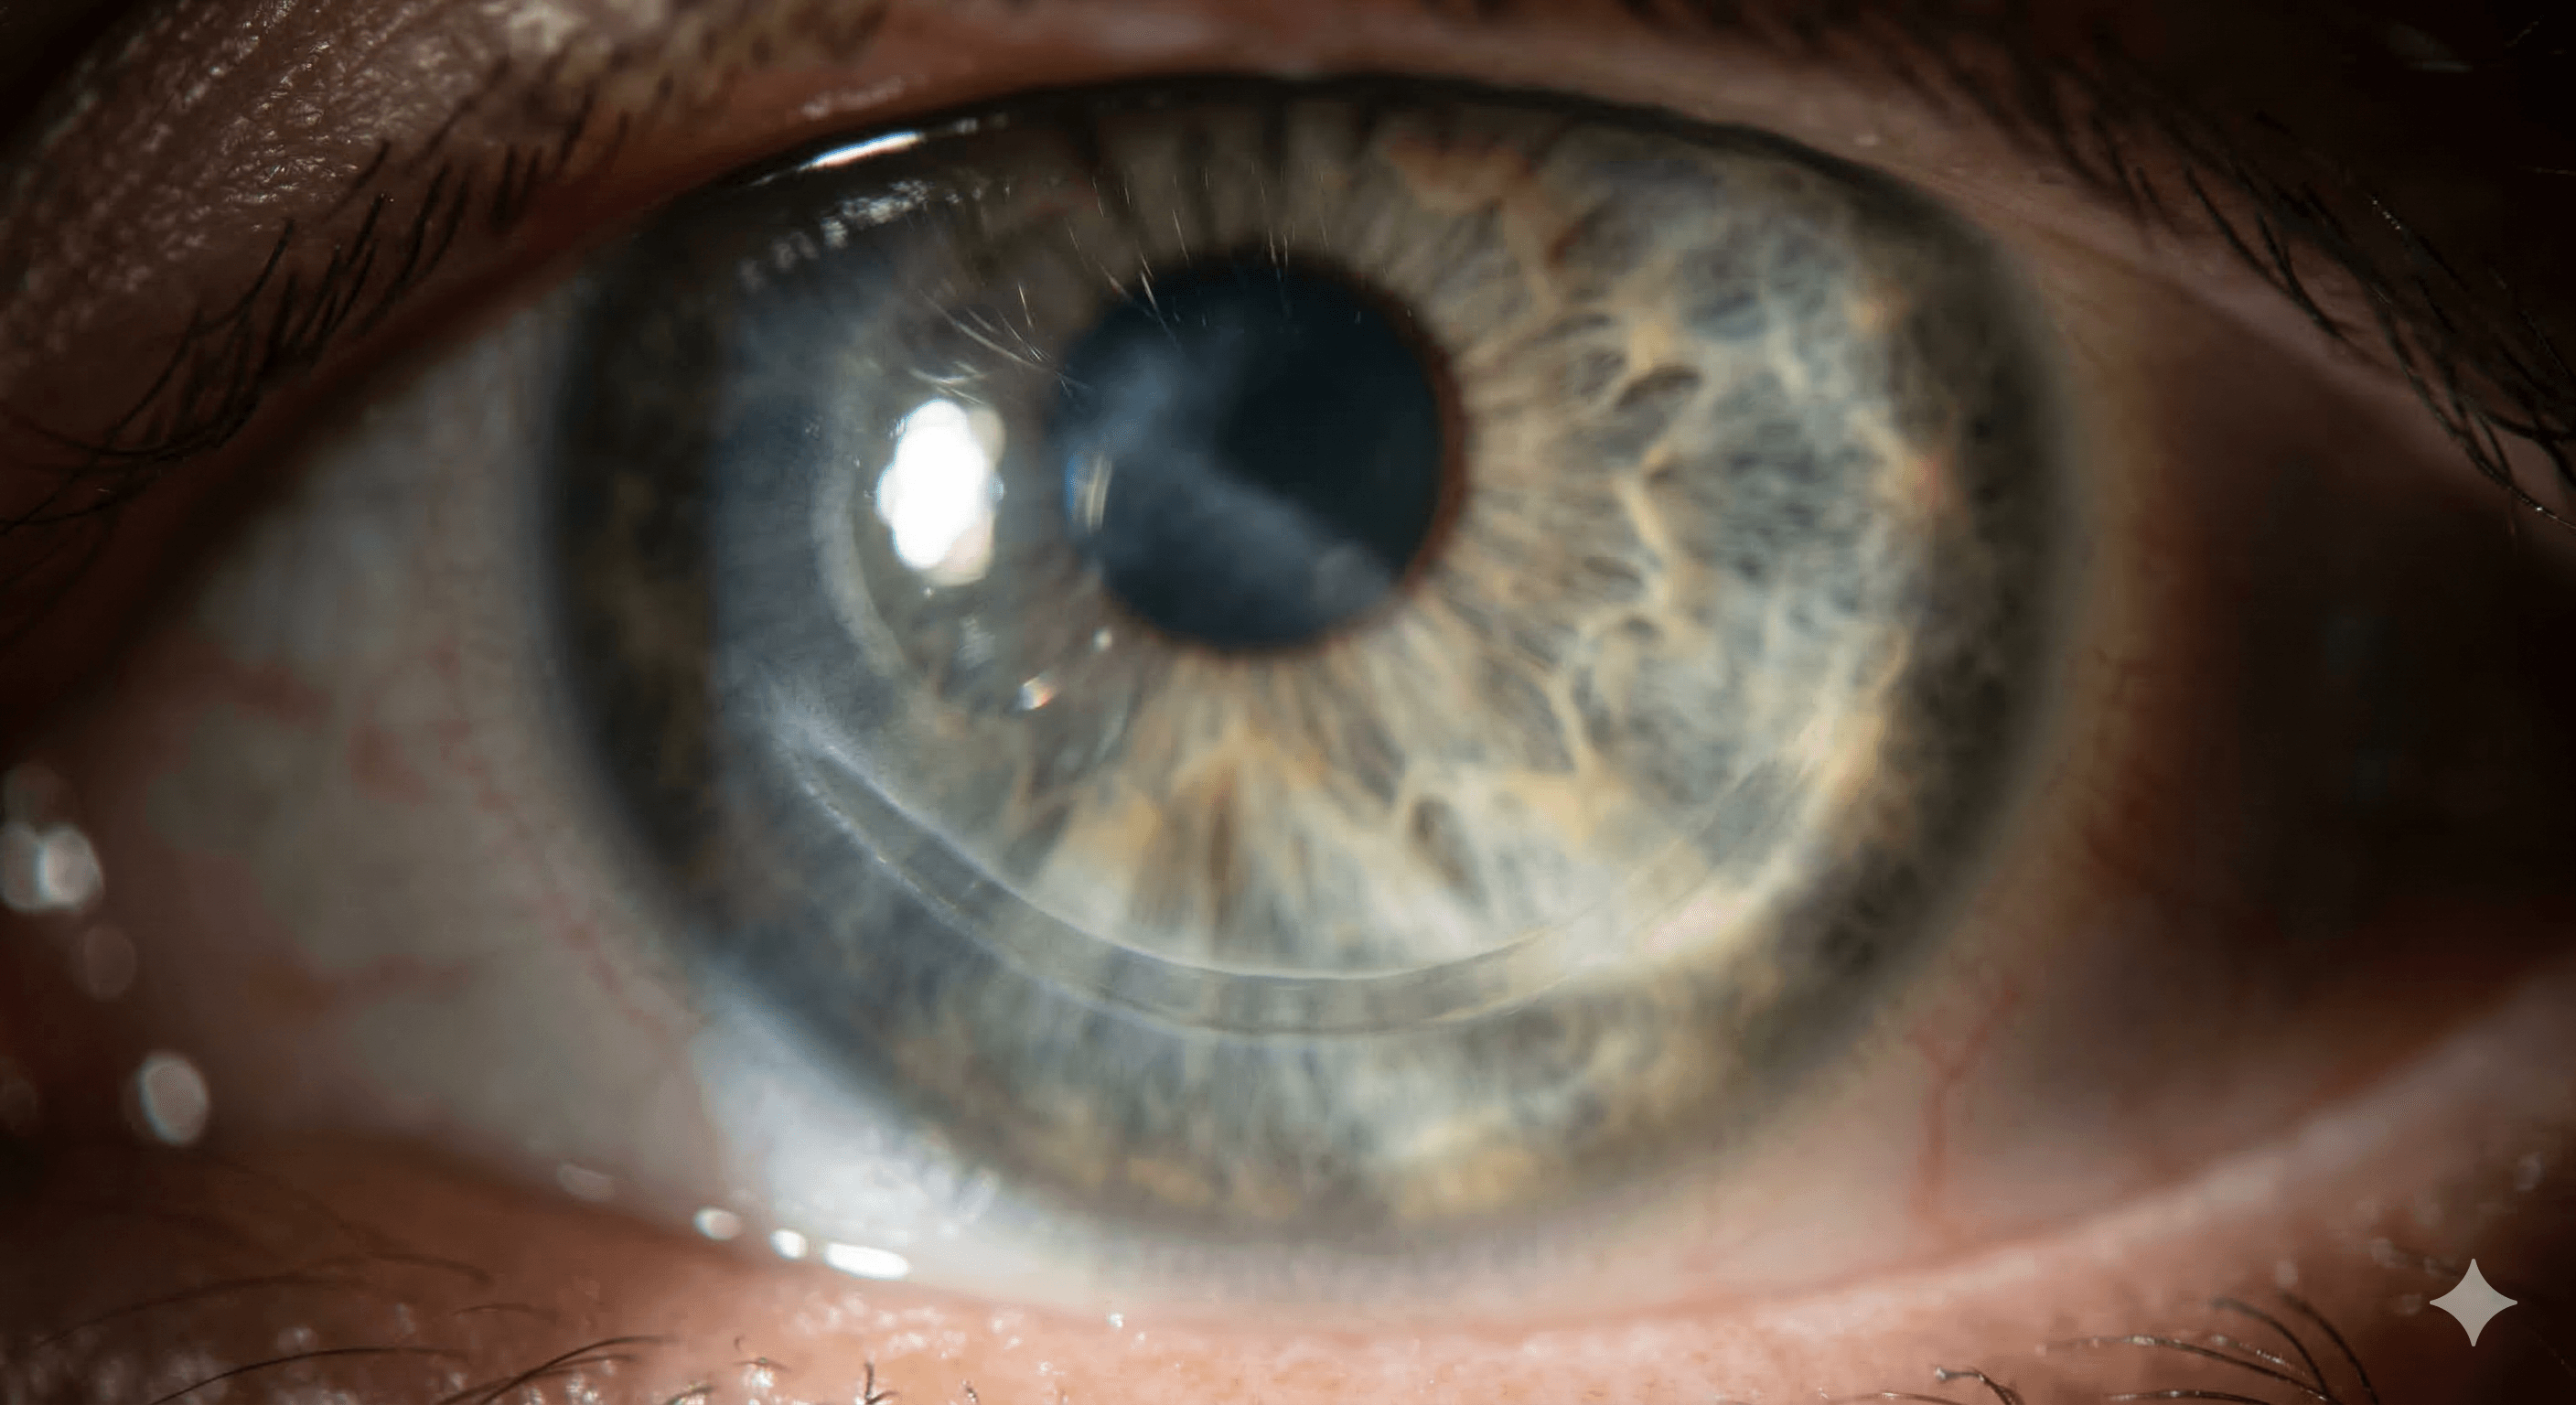

Queratocono

El queratocono es una afección progresiva en la que la córnea se adelgaza y comienza a abultarse en forma de cono, lo que provoca una visión distorsionada.

Degeneración marginal pelúcida

Es un trastorno corneal ectásico poco común, caracterizado por un adelgazamiento periférico en la zona inferior de la córnea que genera un astigmatismo irregular.

Ectasia post lasik

Complicación postoperatoria donde la córnea se vuelve inestable y se abulta hacia adelante tras una cirugía láser, similar a un queratocono inducido.